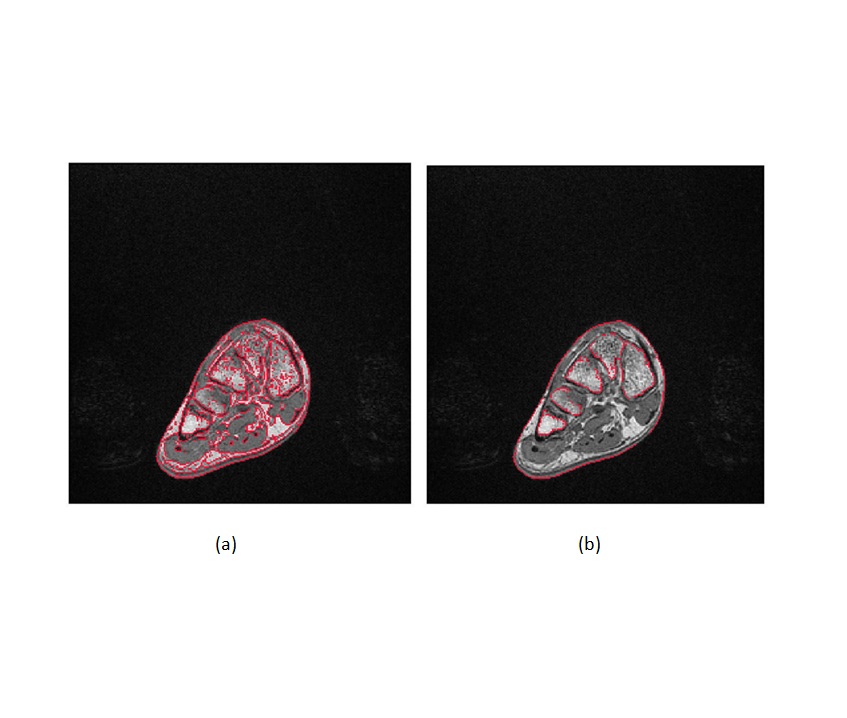

• Figure 1.14

Edges extraction from MRI images (a) Automatic edge detection using Matlab program (b) Selection of only the edges of the bones